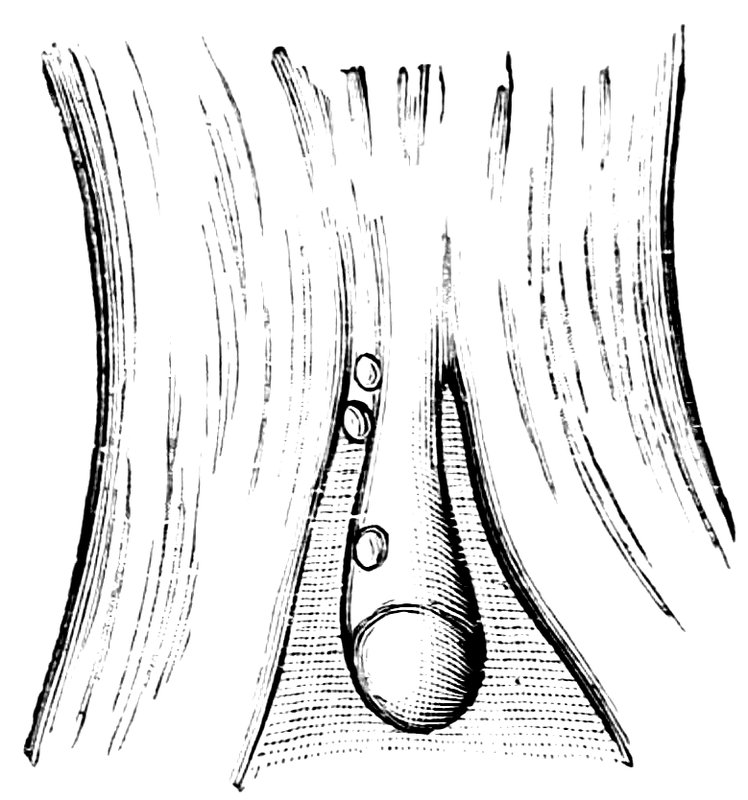

| 13. | The external genital organs of a virgin | 55 |

| 14. | Sagittal section of the female pelvis | 56 |

| 15. | Primitive follicles | 58 |

| 16. | Ripening follicles | 61 |

| 17. | Graafian follicles | 62 |

| 18. | Annular Hymen | 64 |

| 19. | Annular Hymen | 64 |

| 20. | Semilunar Hymen | 65 |

| 21. | Annular Hymen with Congenital Symmetrical Indentations | 65 |

| 22. | Fimbriate Hymen | 65 |

| 23. | Deflorated Fimbriate Hymen | 65 |

| 24. | Septate Annular Hymen | 67 |

| 25. | Septate Semilunar Hymen | 67 |

| 26. | Extremely tough Annular Hymen with an obliquely disposed Septum | 67 |

| 27. | Septate Hymen with Apertures of unequal Size | 67 |

| 28. | Septate Hymen with Apertures of unequal Size | 68 |

| 29. | Hymen with rudimentary Septum | 68 |

| 30. | Hymen with posterior rudimentary Septum | 68 |

| 31. | Labiate Hymen with posterior rudimentary Septum | 68 |

| 32. | Hymen with anterior rudimentary Septum | 69 |

| 33. | Hymen with anterior rudimentary Septum projecting in a opiniform Manner | 69 |

| 34. | Hymen with anterior and posterior rudimentary Septa | 69 |

| 35. | Hymen with filiform Process projecting from the anterior Margin | 69 |

| 36. | Hymen in which there are two symmetrically disposed thinned Areas. The left of these is perforated | 69 |

| 37. | Very unusual form of Hymen | 70 |

| 38. | Semilunar Hymen with cicatrized Lacerations in its Border | 70 |

| 39. | Deflorated Semilunar Hymen with laterally disposed symmetrical Lacerations | 70 |

| 40. | Deflorated Annular Hymen with several cicatrized Lacerations | 70 |

| 41. | A. Septate Hymen in which defloration has been effected through one of the Apertures. U. Urethra. Cl. Clitoris. H. Cicatrized Margin. C. Septum. B. Lateral view of Septum | 70 |

| 42. | Deflorated Septate Hymen | 71 |

| x43. | Hymen with larger anterior and smaller posterior Apertures | 71 |

| 44. | Carunculæ Myrtiformes in a Primipara | 71 |

| 45. | Vaginal Inlet of a Multipara, without Carunculæ Myrtiformes. Slight Prolapse of Anterior and Posterior Vaginal Walls | 71 |